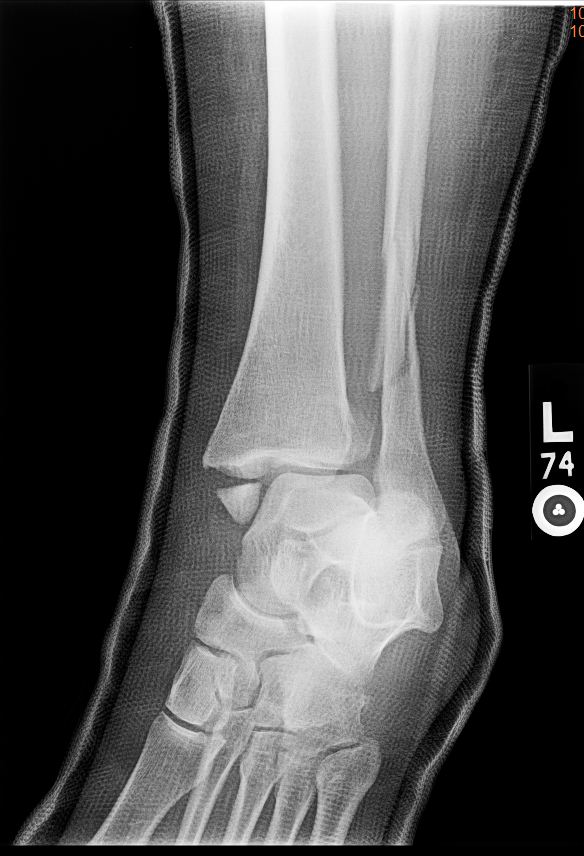

Displaced oblique fracture of the distal tibia with ext ...

Displaced oblique fracture of the distal tibia with ext ... from openi.nlm.nih.gov